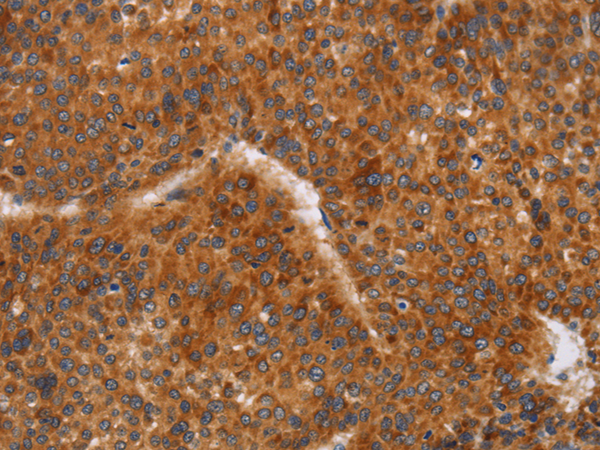

分类: 科研抗体货号: P11628别名: LEC; LMC; NCC4; CKb12; HCC-4; LCC-1; Mtn-1; NCC-4; SCYL4; ILINCK; SCYA16应用: WB,IHC反应种属: Human

分类: 科研抗体货号: P11640别名: T10应用: WB,IHC反应种属: Human

分类: 科研抗体货号: P11626别名: KRS1; MST2/KRS2; MST1; YSK3; TIIAC应用: WB,IHC反应种属: Human, Mouse

分类: 科研抗体货号: P11638别名: CD327; CD33L; OBBP1; CD33L1; CD33L2; CDW327应用: WB,IHC反应种属: Human

分类: 科研抗体货号: P11636别名: LY94; CD335; NKP46; NK-p46应用: WB,IHC反应种属: Human, Mouse

分类: 科研抗体货号: P11664别名: CIB; CIBP; KIP1; PRKDCIP; SIP2-28应用: IHC反应种属: Human, Mouse, Rat

分类: 科研抗体货号: P11634别名: CD30; Ki-1; D1S166E应用: IHC反应种属: Human